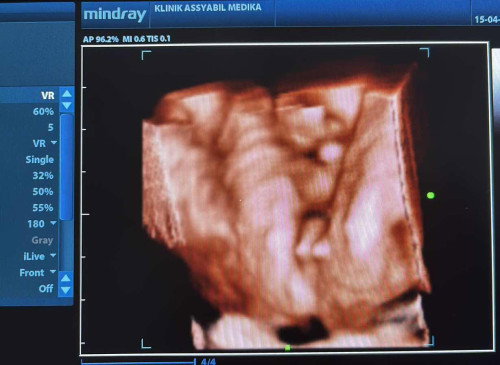

Aku bingung Bun, suami gak kerja udah hampir 2 bulan ini, aku punya anak 2, sekarang lagi hamil anak ke 3 hpl juli. Sementara keluarganya suami bener2 gak ada bantu sama sekali, selama ini kami hidup dari orang tua ku. Ya makan, jajan anak, sampai kami masih tinggal sama orang tua ku. Aku sama suami udah berusaha untuk mencari pekerjaan, tapi belum dapat. Sementara BPJS aja kami belum punya.😭😭 Gimana nanti aku mau lahiran, sedih aku kehidupan kaya gini Bun😭#Sharingdong_Bund #sharing